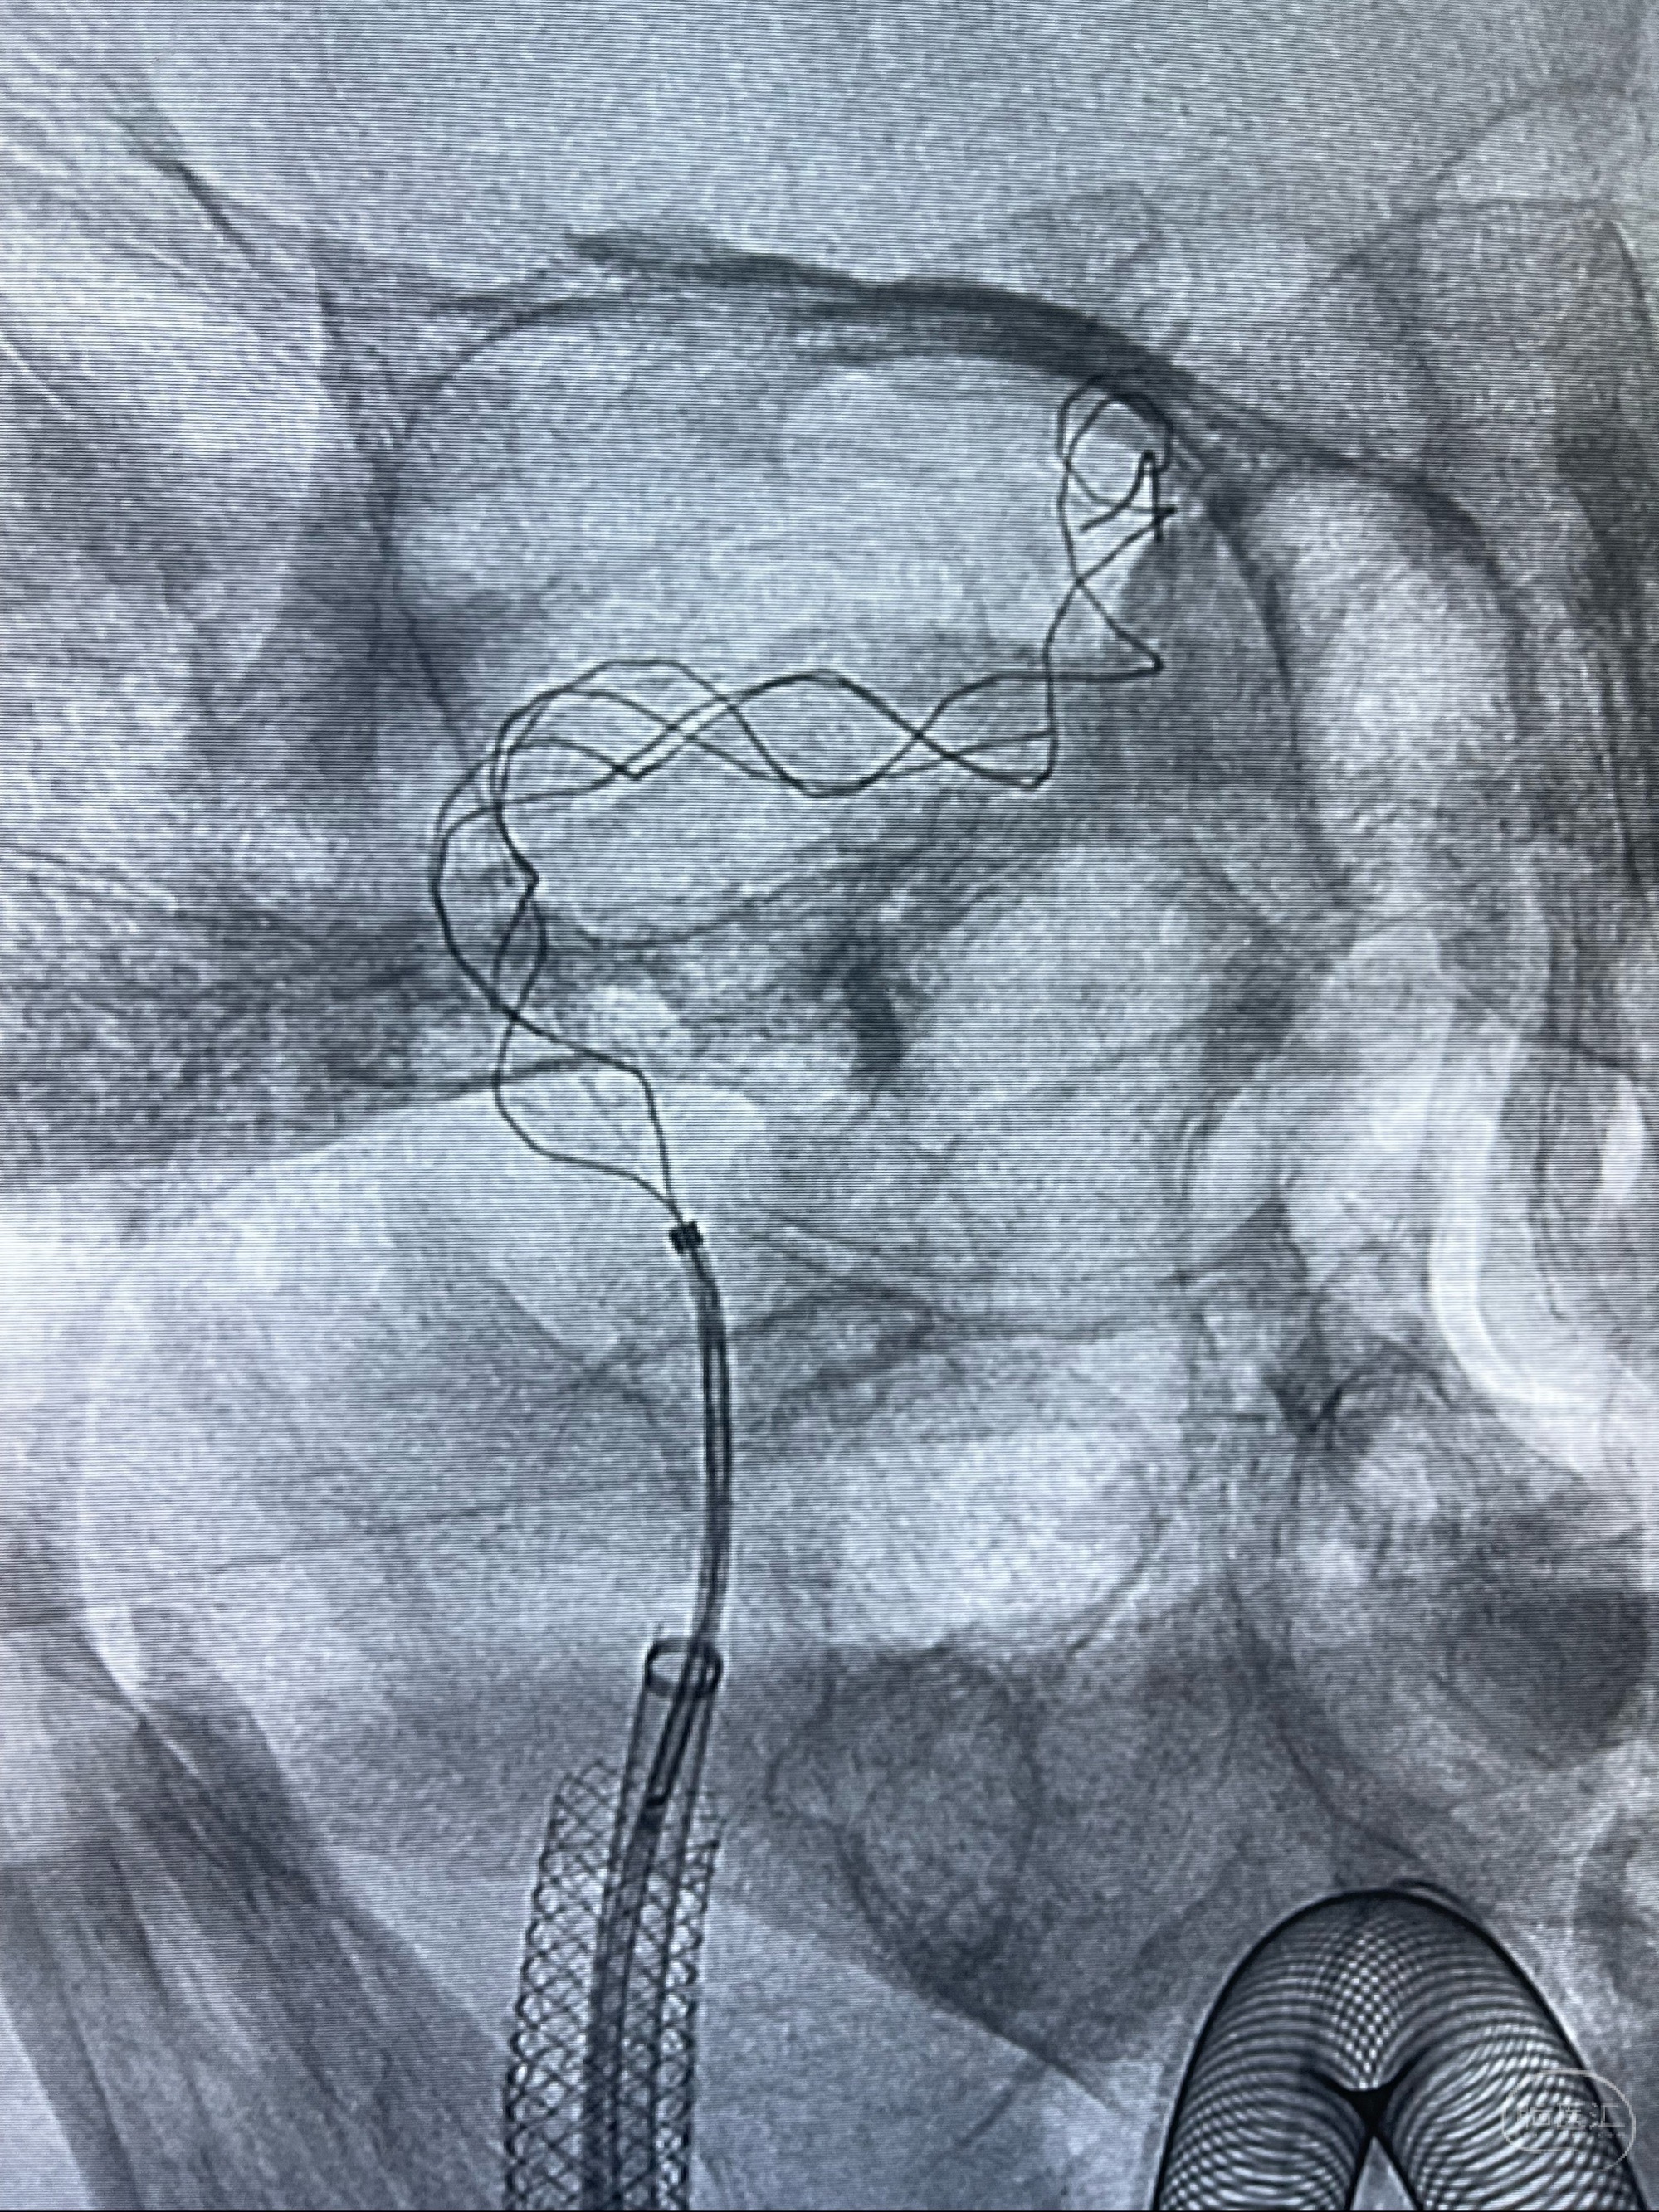

路径图下4-20mm球囊在导丝引导下超选择性至狭窄段,以6-8个大气压扩张,持续30s

泄除球囊造影显示局部管腔扩张佳

后移球囊至颈段狭窄段,以8-12个大气压扩张,持续30s后泄除球囊

即刻造影显示狭窄扩张佳

重新行“路径图”,支架导管在微导丝引导下超选择性插入至右侧颈内动脉眼段,4.5-50mmLeo支架释放,远心端位于海绵窦段,近心端位于岩骨段狭窄段以近

即刻造影显示支架贴壁佳